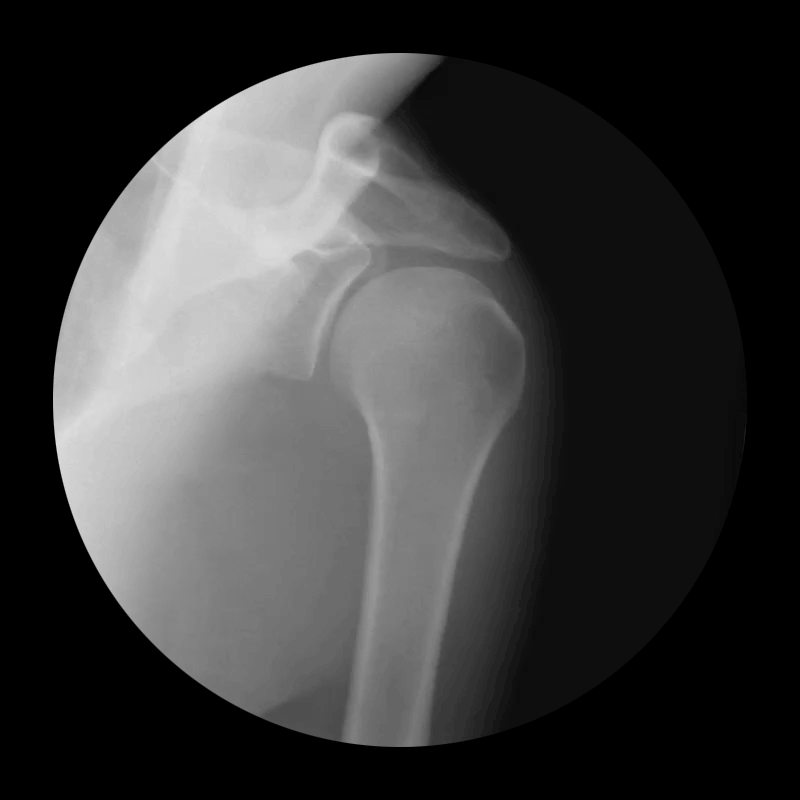

Shoulder

Not everyone has X-ray hardware lying around, so in order to get a beneath-the-skin glimpse of the human body, Drake collaborated with Weiss Orthopaedics of California. He then used Adobe Premiere and Photoshop to turn the video into animated GIFs, and the result is what you see below.

Getting an animated glimpse at the inner workings of the human body has never been easier thanks to a project by designer Cameron Drake. Using the Internet-borne art of the animated GIF, he's created a stunning set of moving X-ray images that are equal parts awesome and strange.